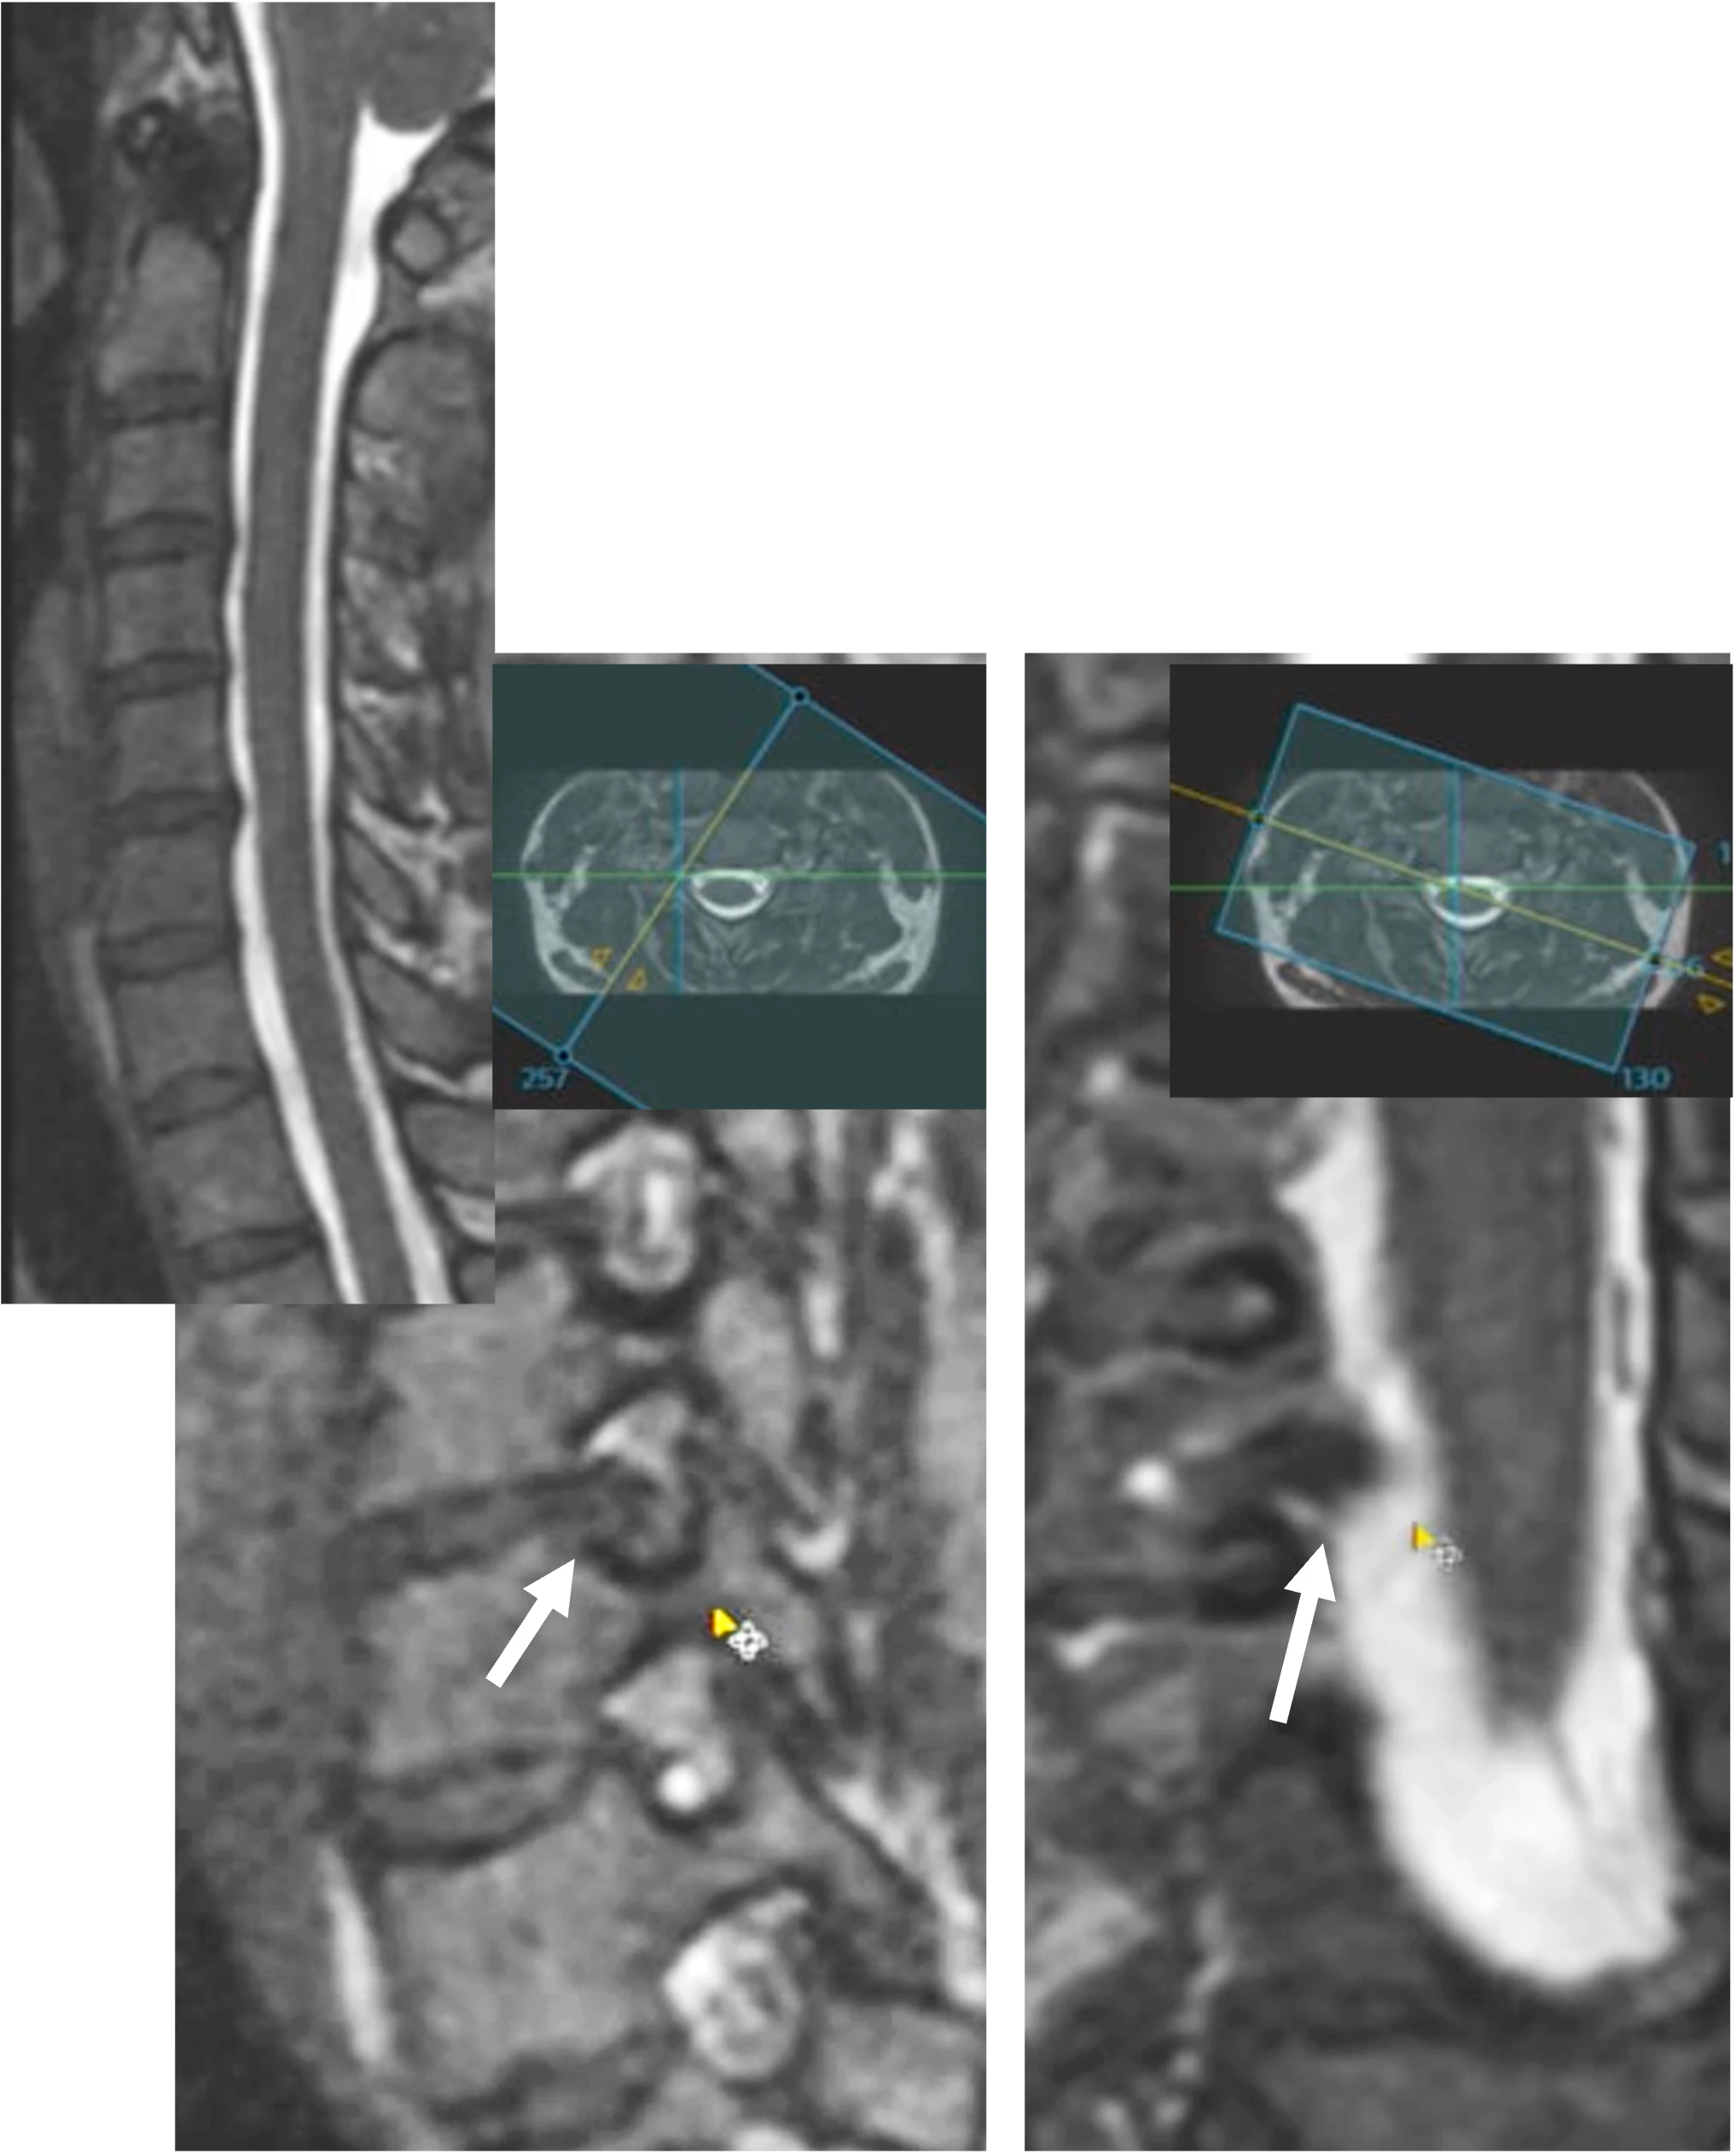

高分解能脊椎3D撮影

通常ではヘルニアの突出部位がはっきりわからないものでも、3D撮影してリアルタイム観察角度変換により、病変を見出します。